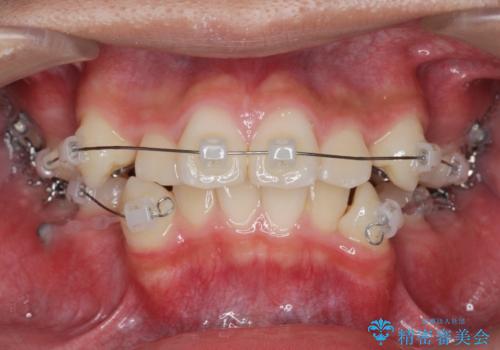

がちゃがちゃした前歯をきれいにしたい

- 前歯のがたつきが原因で歯ブラシしづらい、見た目を改善したい!と矯正治療を希望され来院されました。

スペースの不足が見られるため、小臼歯の4本抜歯を行いマルチブラケットを用いた矯正治療を計画します。

噛み締めが強く、治療に時間がかかりましたが矯正治療の仕上がりに満足いただくことができました。